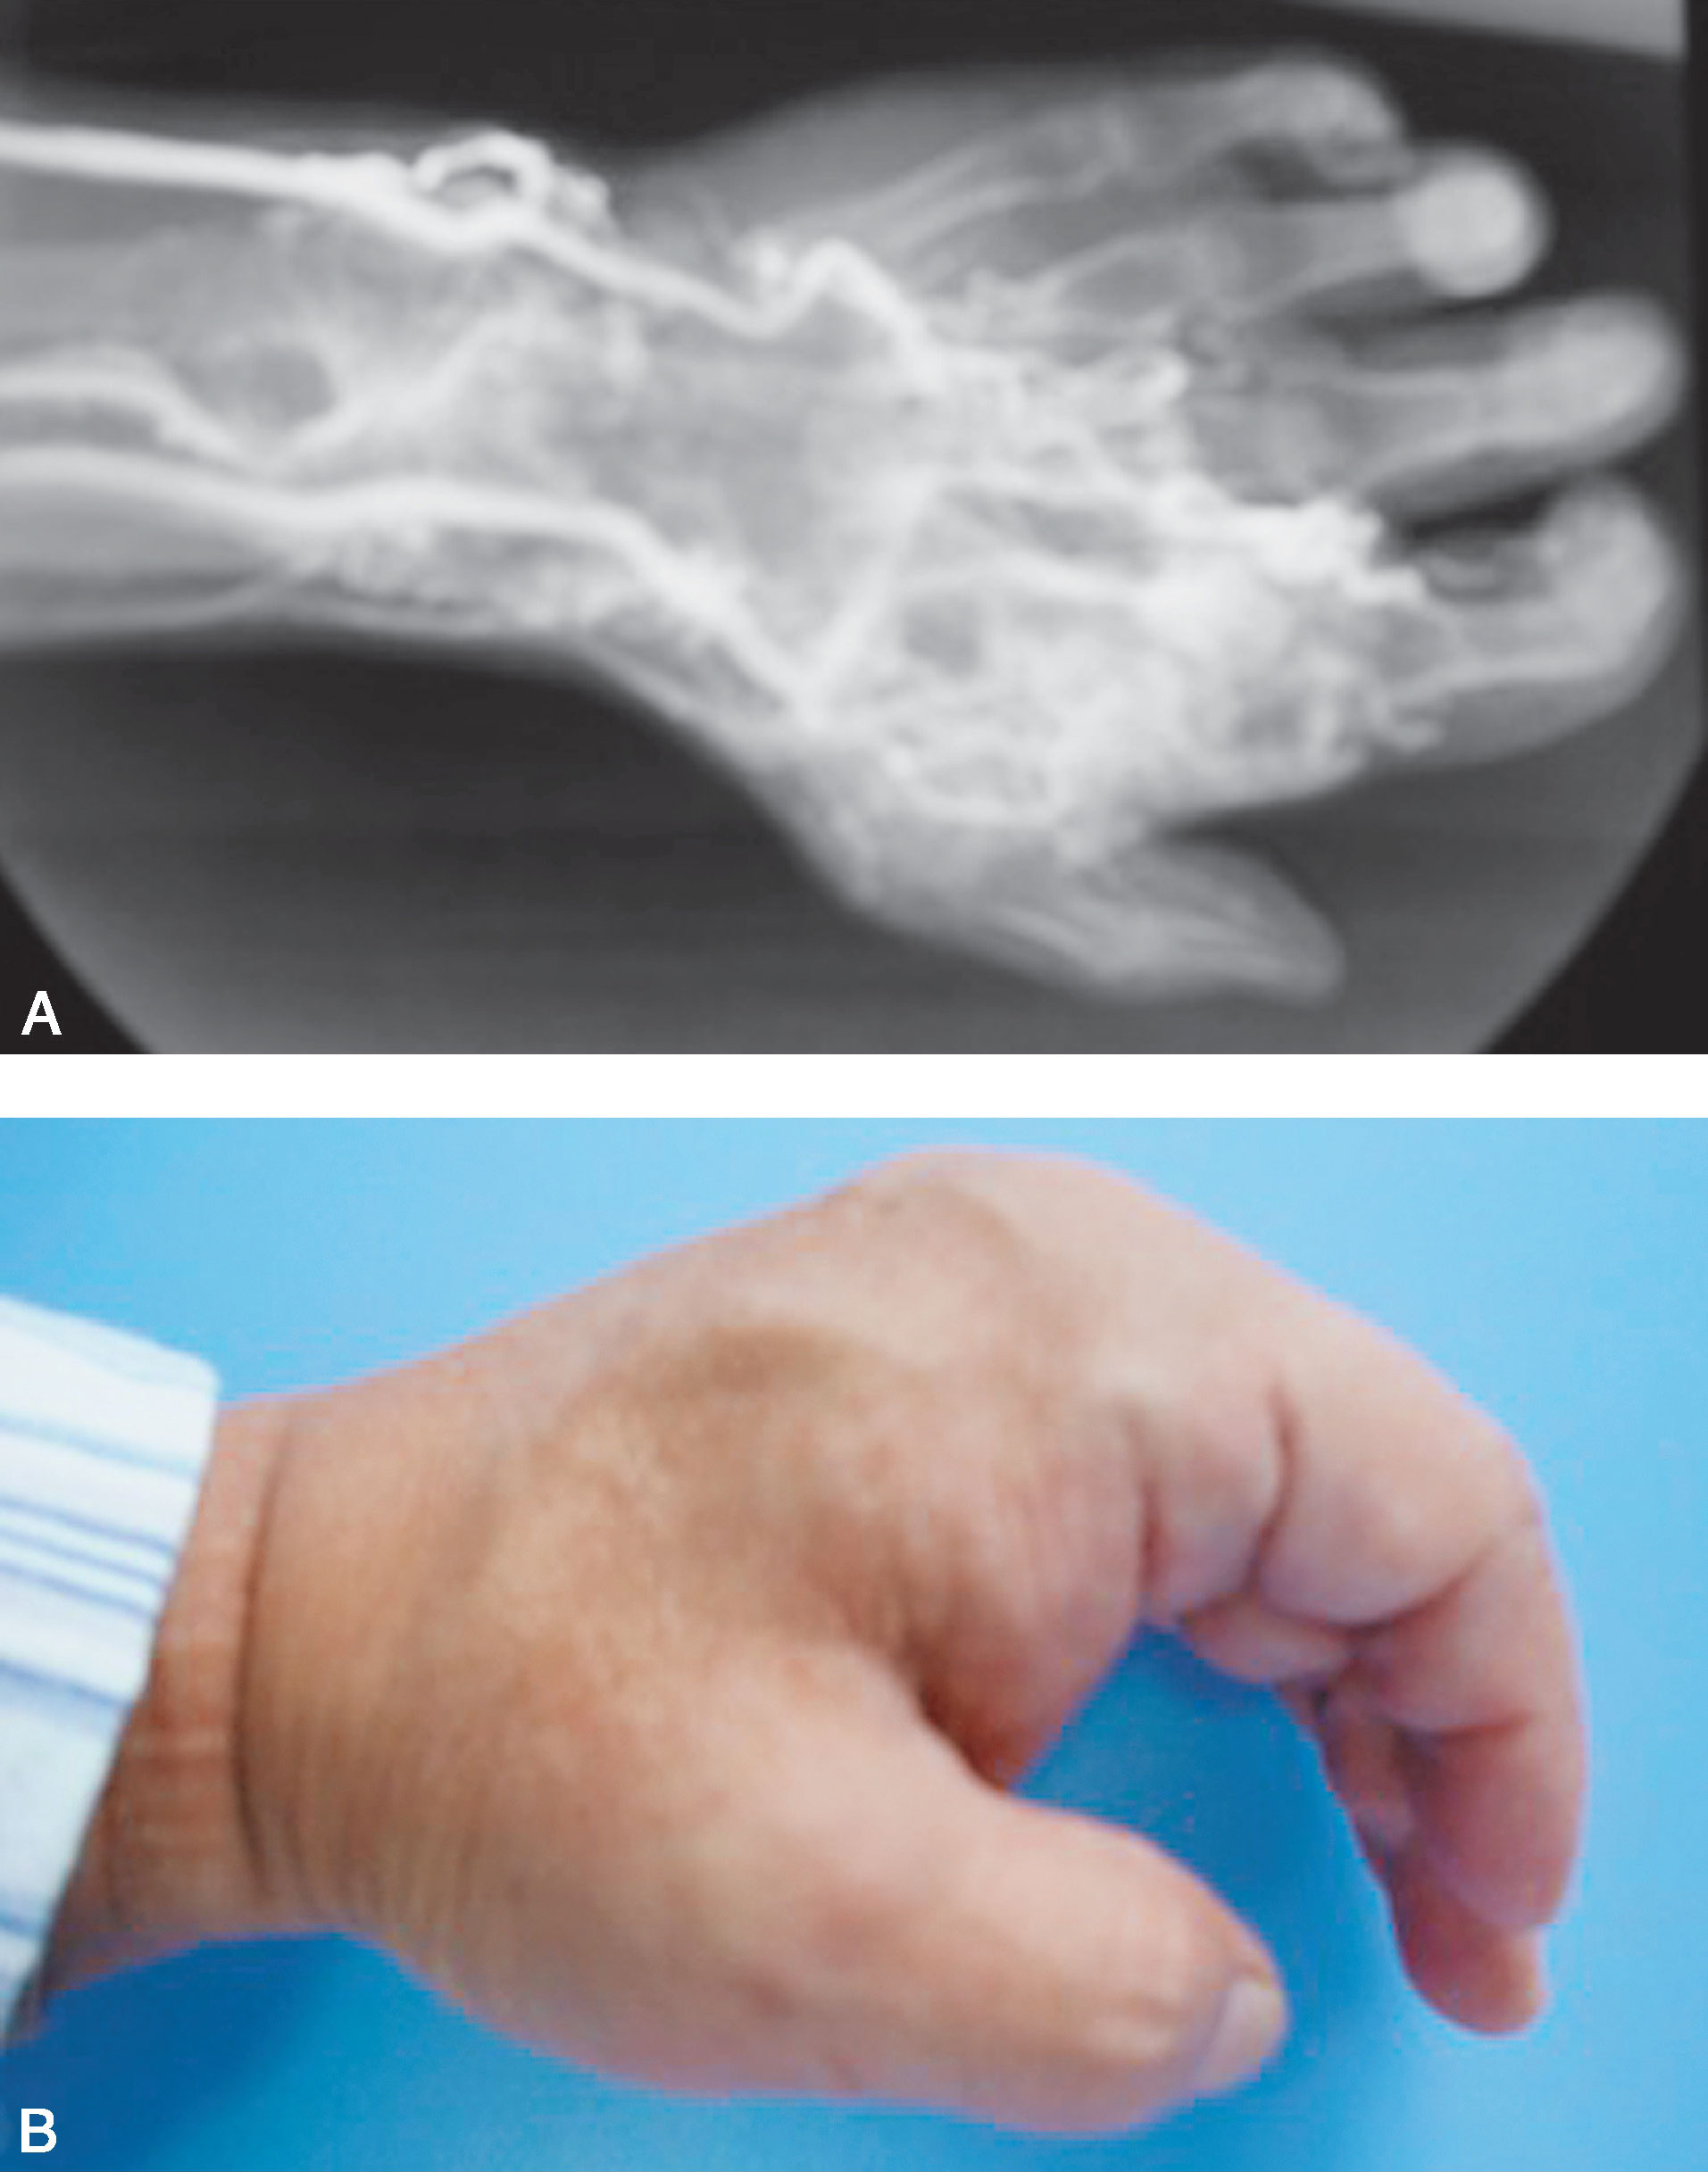

A.右侧拇指发育不良,大鱼际缺如(侧面观);B.掌面观显示大鱼际缺如,拇指内收、旋后

图1-2-7 右侧拇指发育不良及大鱼际缺如